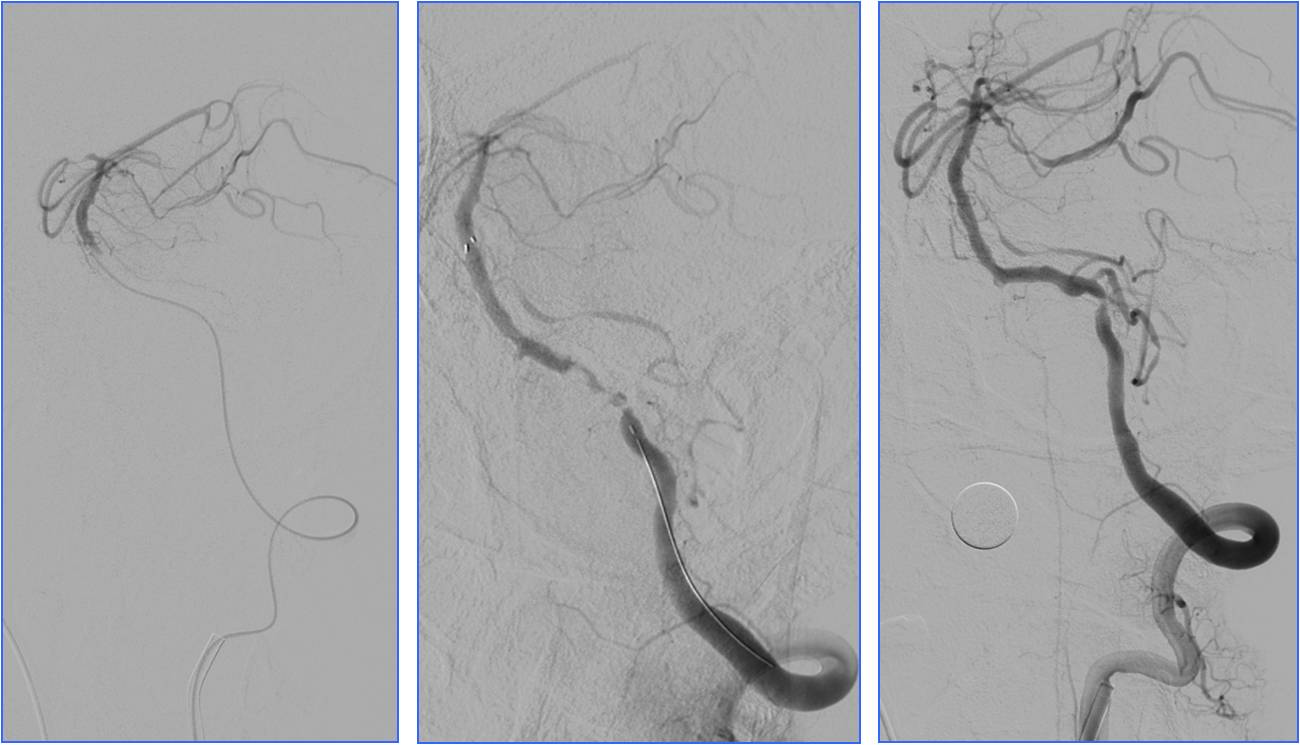

Case4 基底动脉支架置入

》男,60岁。既往高血压病史。

》因“言语不清、右侧肢体无力1小时”于9:00到急诊就诊。

》查体:血压140/90mmHg。神志清,运动性失语,右侧肢体肌力3级,右侧巴氏征阳性。NIHSS评分6分。

》头CT检查未见出血(9:19)。

》9:50给阿替普酶静脉溶栓,5mg静推,余45mg持续泵入。

》半小时内患者症状完全缓解。

》11:00突发意识不清。

》11:11复查头CT。

》11:56头MRA。

▼11:11复查头CT

▼11:56头MRA

》准备介入血管内治疗,患者症状自行缓解。后又加重,症状波动2次。

》13:22进入导管室行血管内治疗。行气管插管全身麻醉。

》DSA见基底动脉闭塞,Solitaire支架取栓后见基底动脉重度狭窄,Gateway球囊扩张,置入Wingspan支架。

》术后24h完全恢复,NIHSS评分0分。

▼13:49DSA

▼支架取栓后基底动脉残余重度狭窄

▼基底动脉支架置入术

▼4天后复查MRA